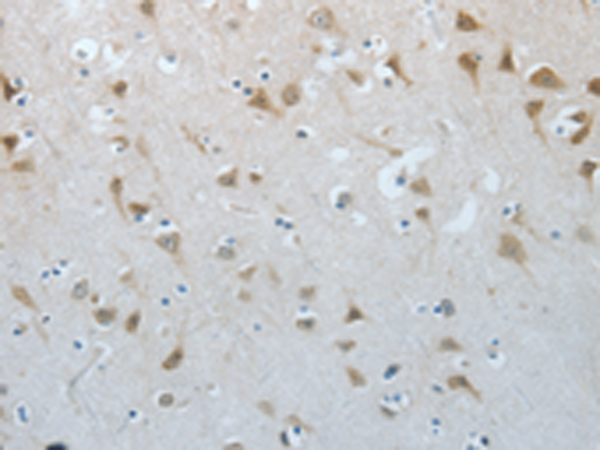

分类: 科研抗体货号: P00563别名: NGFB; HSAN5; Beta-NGF应用: IHC反应种属: Human, Mouse, Rat